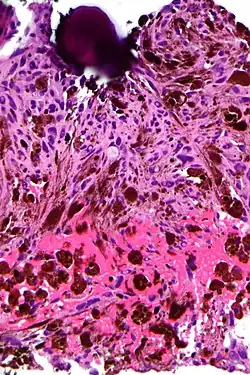

Psammoma body

A psammoma body is a round collection of calcium, seen microscopically. The term is derived from Greek άμμος (ámmos) 'sand'.

Psammoma bodies usually have a laminar appearance, are circular, acellular and basophilic.